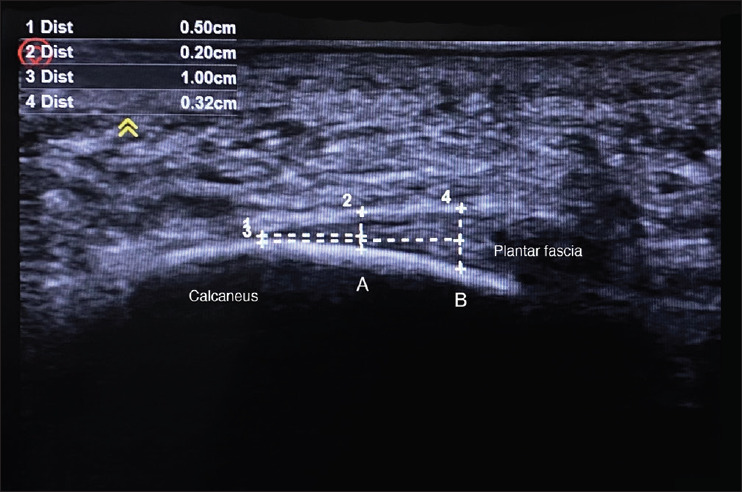

Methods: This cross-sectional study was conducted between January and March 2023, and subjects were through a simple random sampling method. The inclusion criteria were subjects aged 18-35 years old, while those with a history of foot pain, trauma, surgery, special orthosis during pregnancy, and other complications were excluded. Fascia thickness was measured at 10 mm distal from the insertion in the calcaneus. Age, BMI, AHI, gestational age, and pregnancy history were recorded. Student's t-tests were used to compare both groups.

Results: The average plantar fascia thickness in pregnant women was 2.67 ± 0.44 mm in both feet, while in nulliparous, it was 2.24 ± 0.41 mm and 2.26 ± 0.37 mm in the right and left foot, respectively. A significant difference was observed between the two groups based on BMI category (P < 0.05). Women who had experienced more than one pregnancy showed thicker fascia (P < 0.05). In multivariate analysis, BMI (B coefficient: 0.029-0.031, P < 0.05) and number of pregnancies (0.268-0.267, P < 0.05) had a significant effect on plantar fascia thickness in pregnant women, while age and BMI affected nulliparous.